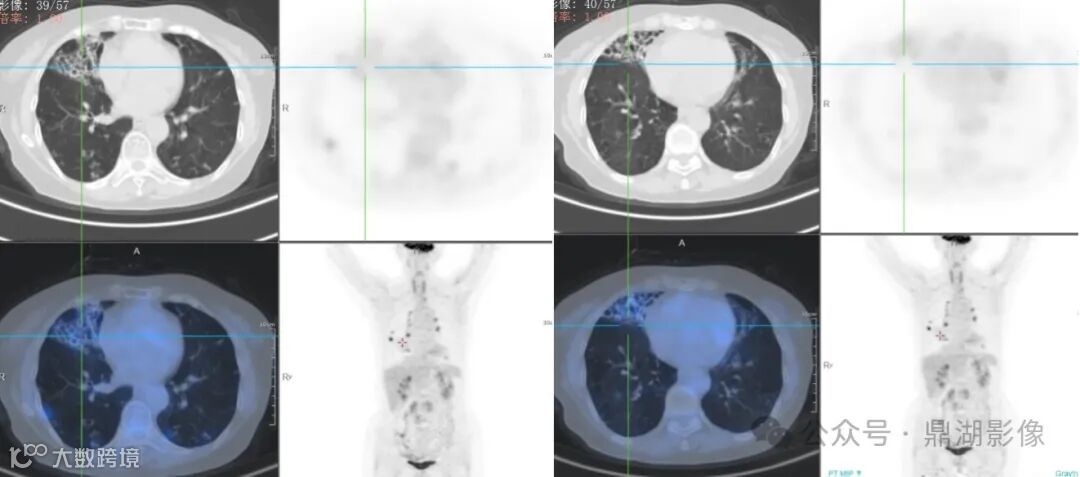

双肺多发支气管扩张伴感染,以右肺中叶、左肺上叶下舌段为著;余双肺散在多发小结节、小结片及小斑片影,部分代谢轻度增高,考虑感染性病变;

双肺门多发淋巴结,代谢异常增高,考虑淋巴结炎。

NTM行FDG显像一般代谢轻度增高;结核性肉芽肿FDG显像常显示代谢异常增高